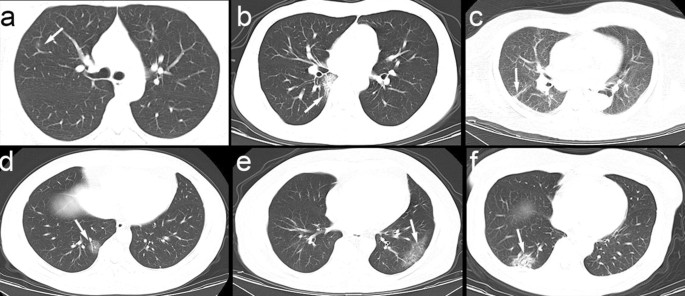

Of all 150 COVID-19 pneumonia patients in this study, their pulmonary lesions had 3 main morphologies, including 18 cases (12.00%) of ground-glass nodules < 10 mm (Fig. 1a), 124 cases (82.67%) of patchy GGO with or without consolidation (Fig. 1b), and 8 cases (5.33%) of cord-like lesions (Fig. 1c). Some patients had multiple imaging manifestations. There were 12 patients (8.00%) who also had thickening of the bronchovascular bundles in the lesions (Fig. 1d), 53 patients (35.33%) with adjacent pleural thickening and interlobular septum thickening presenting as the crazy-paving sign (Fig. 1e), and 54 patients (36.00%) whose CT images showed the air bronchogram sign (Fig. 1f). In addition, 6 cases (4.00%) exhibited pleural effusion, and 2 cases (1.33%) exhibited enlarged lymph nodes.

Fig. 1

figure 1

Various lesions shown on CT images of the included patients. The white arrows indicate the abnormalities. a Ground-glass nodules < 10 mm. b Subsegmental areas of consolidation. c Cord-like lesions. d Thickening of the bronchovascular bundles in the lesions. e Adjacent pleural thickening and interlobular septum thickening presenting as the crazy-paving sign. f Air bronchogram sign